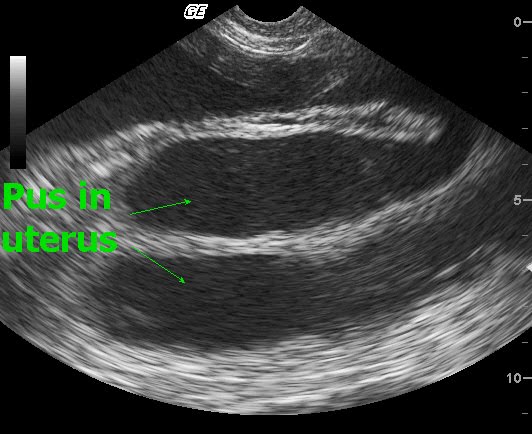

Пиометра у собаки УЗИ диагностика - YouTube

Эндометриты и пиометры. Эндометрит - воспаление слизистой оболочки матки. Во вре

УЗИ, МРТ, КТ при эндометрите

УЗИ при эндометрите